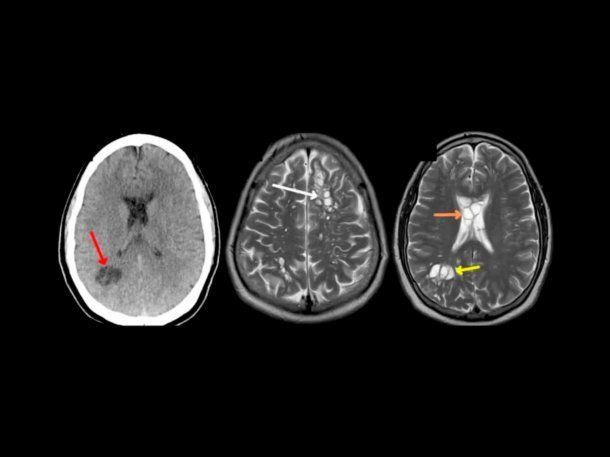

En una tomografía se logró visualizar una gran cantidad de quistes en la cabeza. La neurocisticercosis es común entre las personas que viven en países con malas condiciones sanitarias o están en constantes contacto con cerdos, el animal de donde se contagia el parásito.